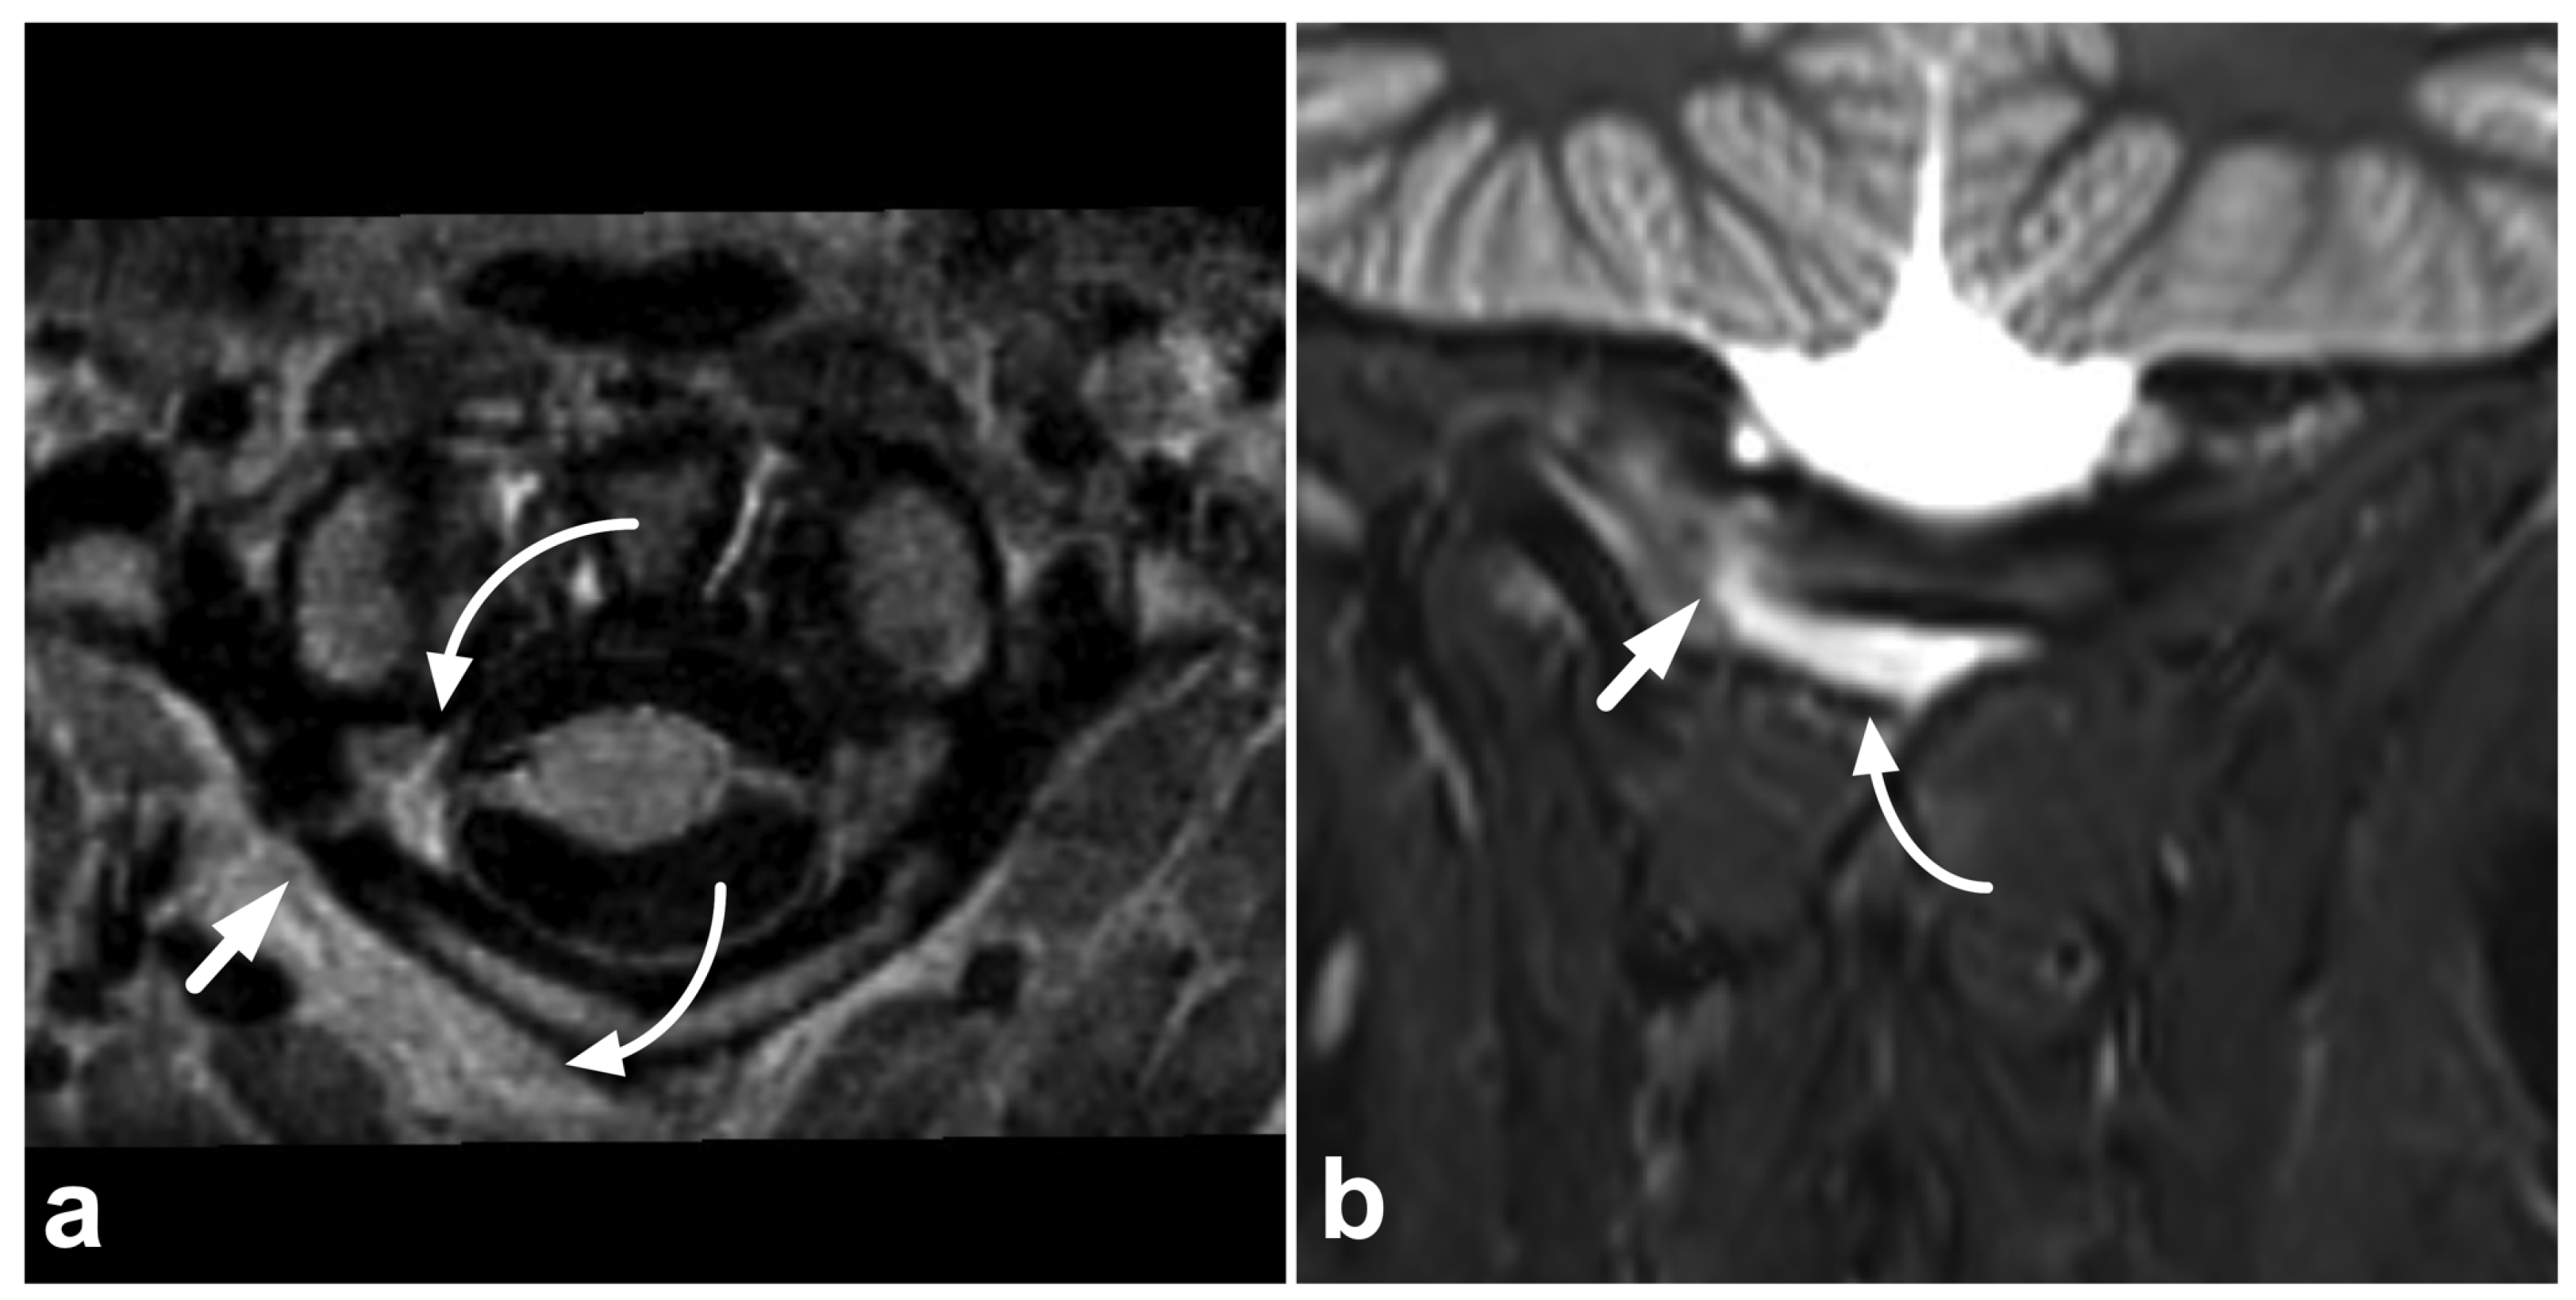

4.1. Occipitocervical and Atlantoaxial Ligaments